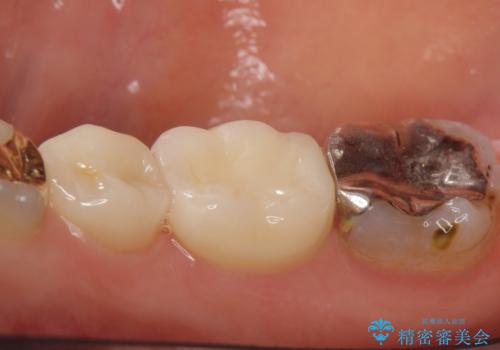

- 右下でものを咬むと歯茎が疼くので診て欲しいといらっしゃった方の症例です。

診査の結果右下6の歯の神経が死んでいたため、根管治療を行いました。

その後症状の消失を確認し、オールセラミッククラウンによる補綴を行いました。

今回用いたオールセラミッククラウンはジルコニアフレームという白い素材の上にセラミックを盛っているため、審美性が非常に高いのが特徴です。

また、ジルコニアは人工ダイヤモンドの材料にも使われているほど高い強度を持っており、そのためオールセラミッククラウンは審美性だけでなく、奥歯やブリッジの補綴も可能とするクラウンです。